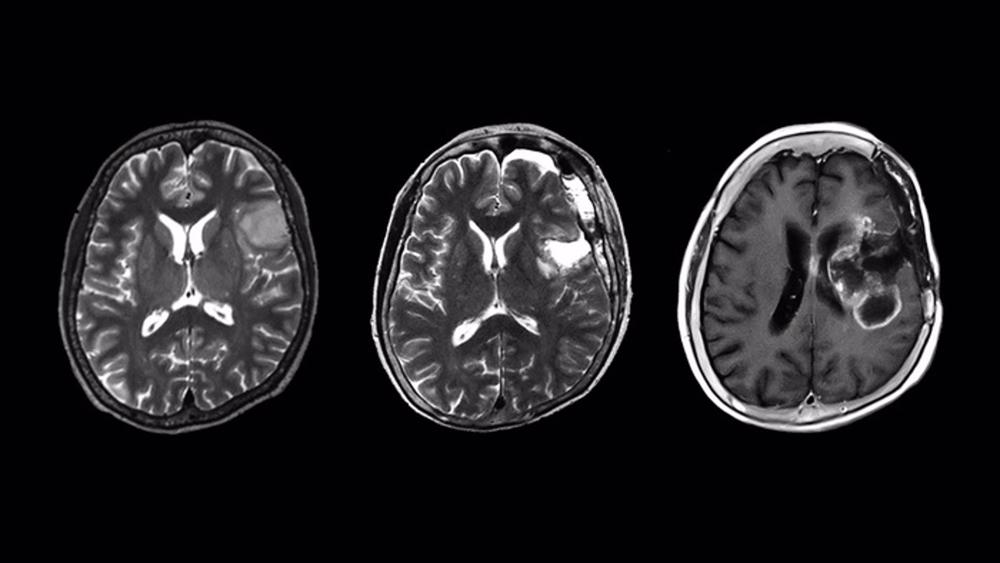

Los gliomas son tumores que se originan en las células gliales que rodean las neuronas del cerebro. Bajo el microscopio, los gliomas se pueden dividir en varios tipos según el tipo de células que invaden. Entre ellos se incluyen los astrocitomas que, como su nombre indica, infectan los astrocitos, un tipo importante de neurona.

En 2016, para mejorar el pronóstico y el manejo de los pacientes, la clasificación de la OMS de tumores del sistema nervioso central incluyó una nueva clasificación de ’gliomas difusos’, basada en la presencia o ausencia de mutaciones específicas. Dos tipos raros de astrocitomas difusos son los astrocitomas difusos de isocitrato deshidrogenasa de tipo salvaje (IDHwt) infiltrantes y localizados. Dado que son tan raros, falta información sobre si las características infiltrativas o localizadas afectan su pronóstico y lo que esto significa para el paciente.

El equipo de investigación de la Universidad de Nagoya, dirigido por Yuji Kibe y Kazuya Motomura del Departamento de Neurocirugía, analizó los astrocitomas IDHwt localizados y descubrió que todos resultaron en una recurrencia maligna y un pronóstico clínico precario similar al de los glioblastomas. Los glioblastomas se encuentran entre los tumores más malignos, con un tiempo de supervivencia promedio de 8 meses y menos del 7 por ciento de los pacientes sobreviven cinco años.